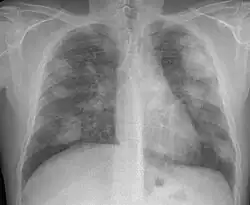

Complicated silicosis

Silicosis can become "complicated" by the development of severe scarring (progressive massive fibrosis, or also known as conglomerate silicosis), where the small nodules gradually become confluent, reaching a size of 1 cm or greater. PMF is associated with more severe symptoms and respiratory impairment than simple disease. Silicosis can also be complicated by other lung disease, such as tuberculosis, non-tuberculous mycobacterial infection, and fungal infection, certain autoimmune diseases, and lung cancer. Complicated silicosis is more common with accelerated silicosis than with the chronic variety.

Acute silicosis

Silicosis that develops a few weeks to 5 years after exposure to high concentrations of respirable silica dust. This is also known as silicoproteinosis. Symptoms of acute silicosis include more rapid onset of severe disabling shortness of breath, cough, weakness, and weight loss, often leading to death. The x-ray usually reveals a diffuse alveolar filling with air bronchograms, described as a ground-glass appearance, and similar to pneumonia, pulmonary edema, alveolar hemorrhage, and alveolar cell lung cancer.